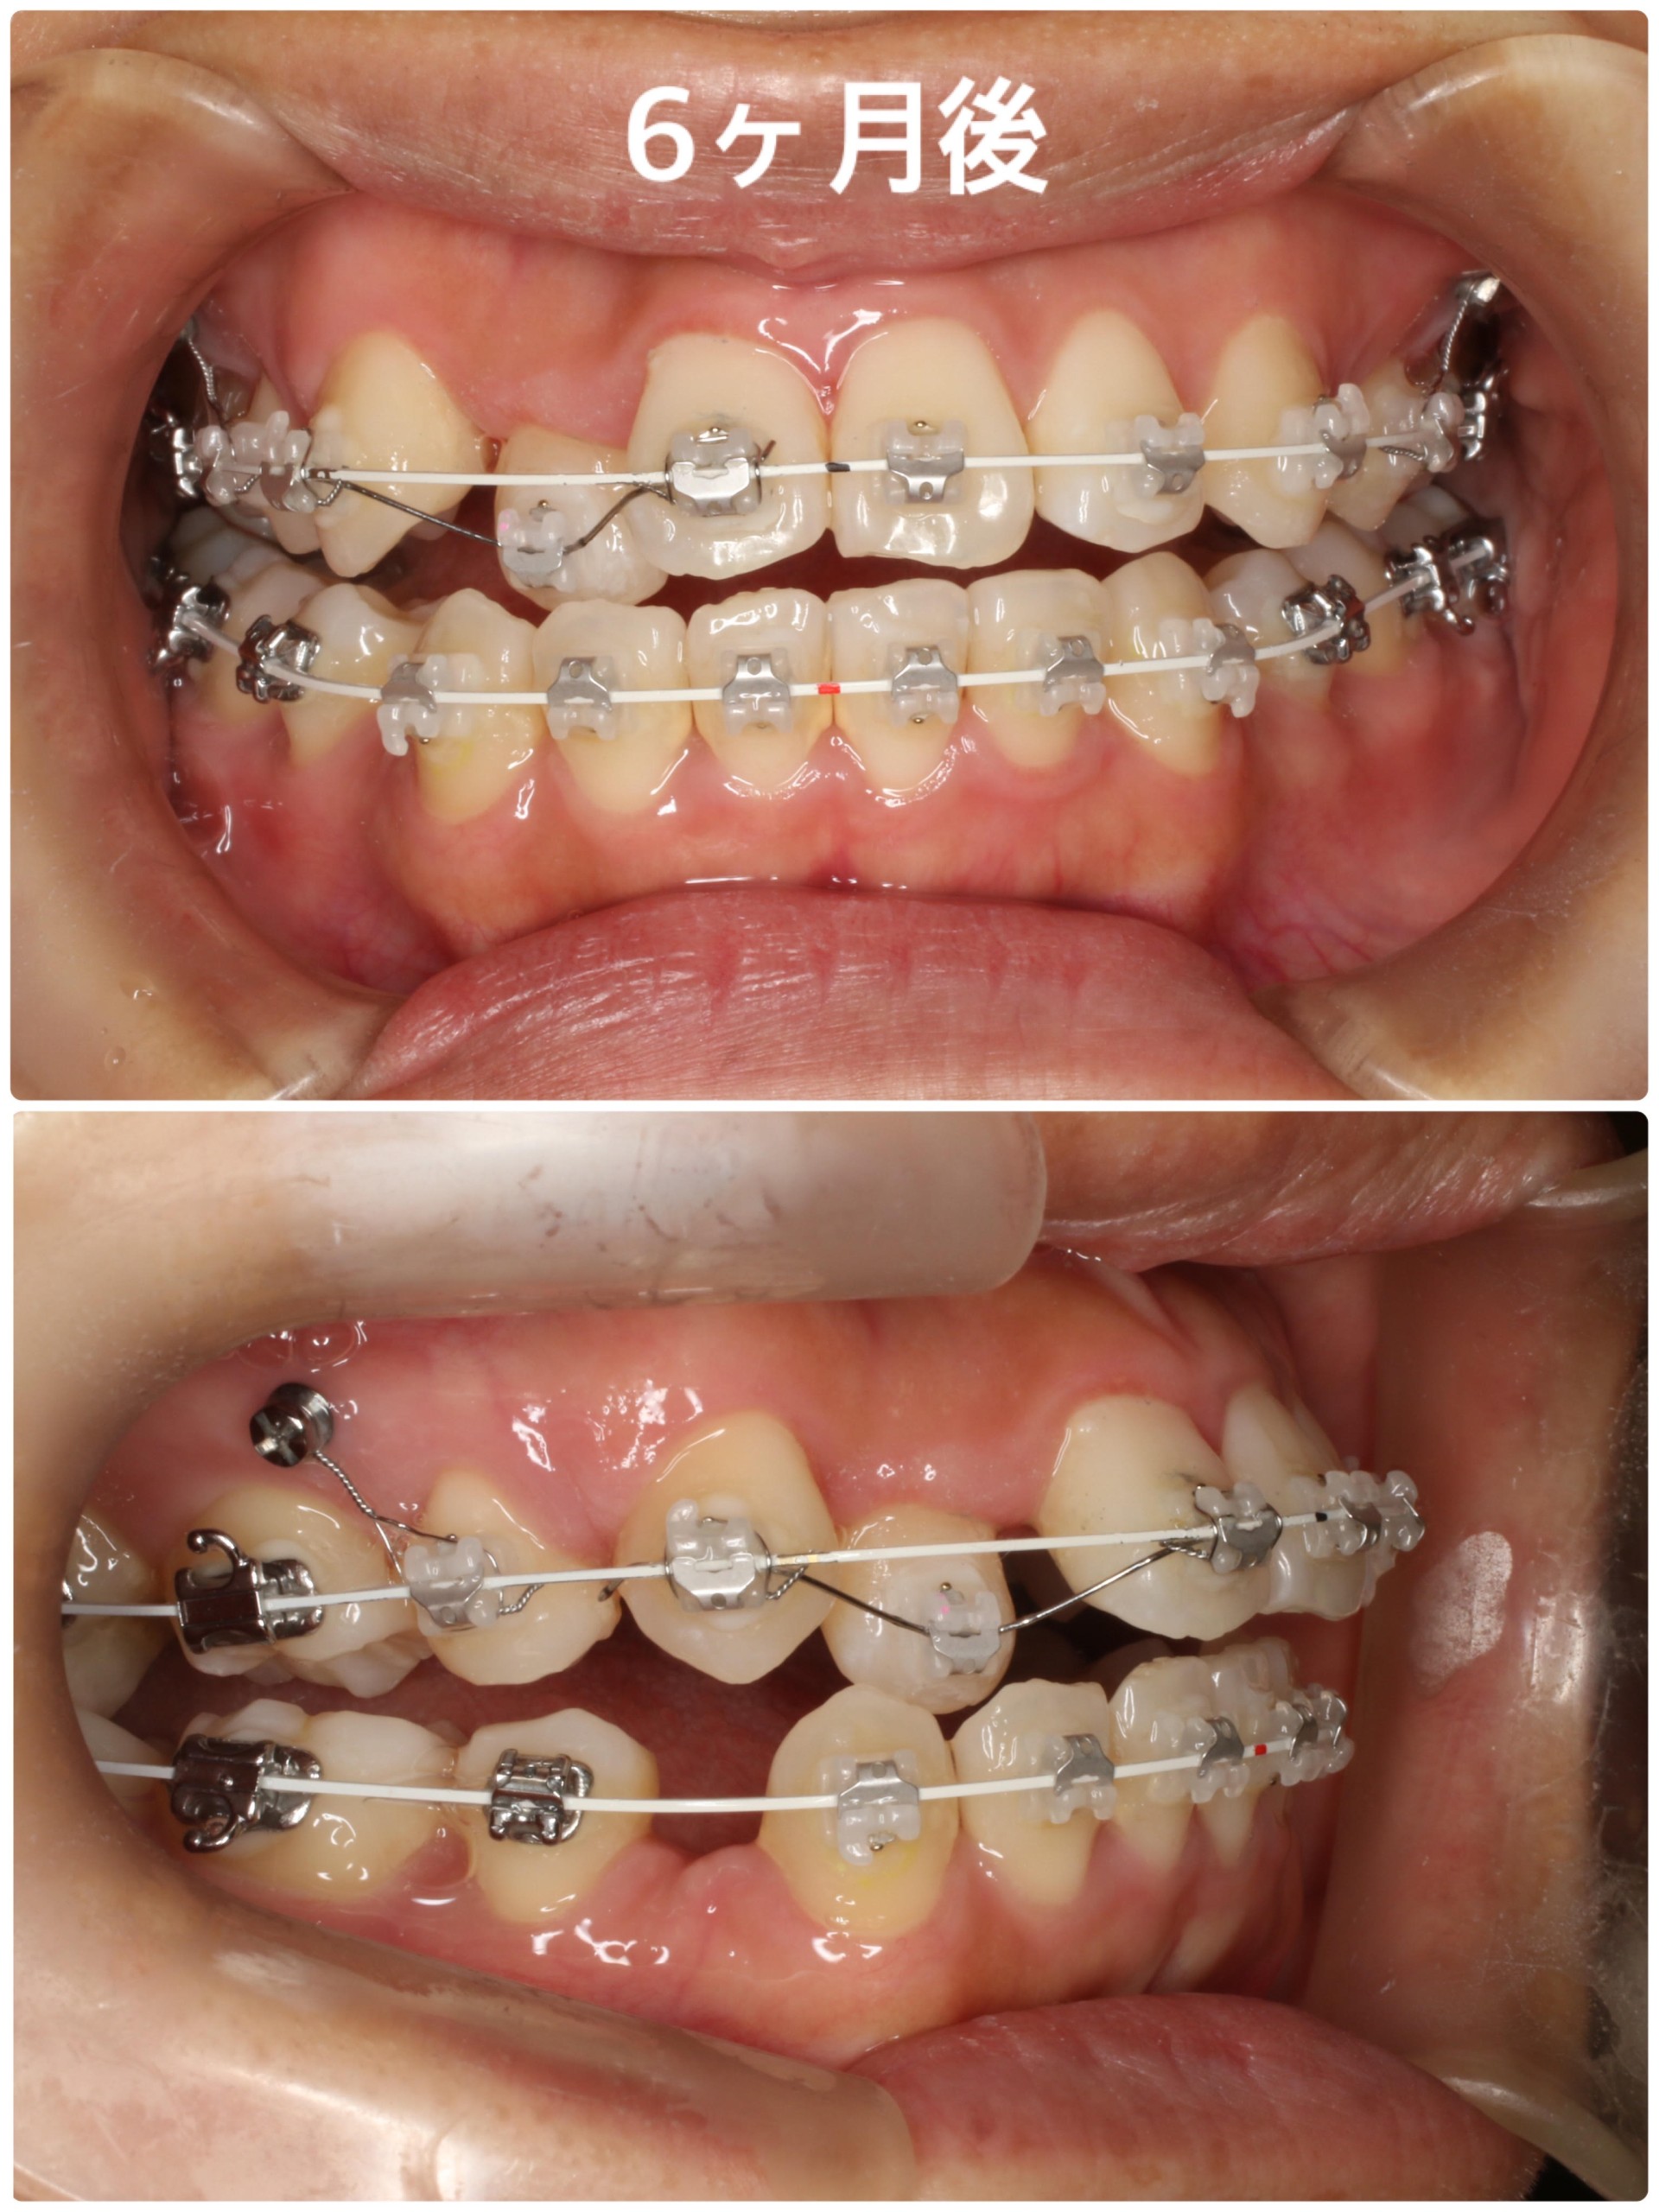

【半年後】

だいぶ上下の叢生が改善されたことが分かりますね!一番叢生が強かった上顎右側の2番は当初左右の歯が重なっていて装置を着けることができなかったため、治療開始から約5カ月後のある程度周囲の歯が動いた時点で装置を着けています。

また、この歯は他の歯に比べてまだ奥の方に引っ込んでいるので、手前に引っ張り出すためにメインの太いワイヤーとは別に細いワイヤーを通して歯を動かしています。